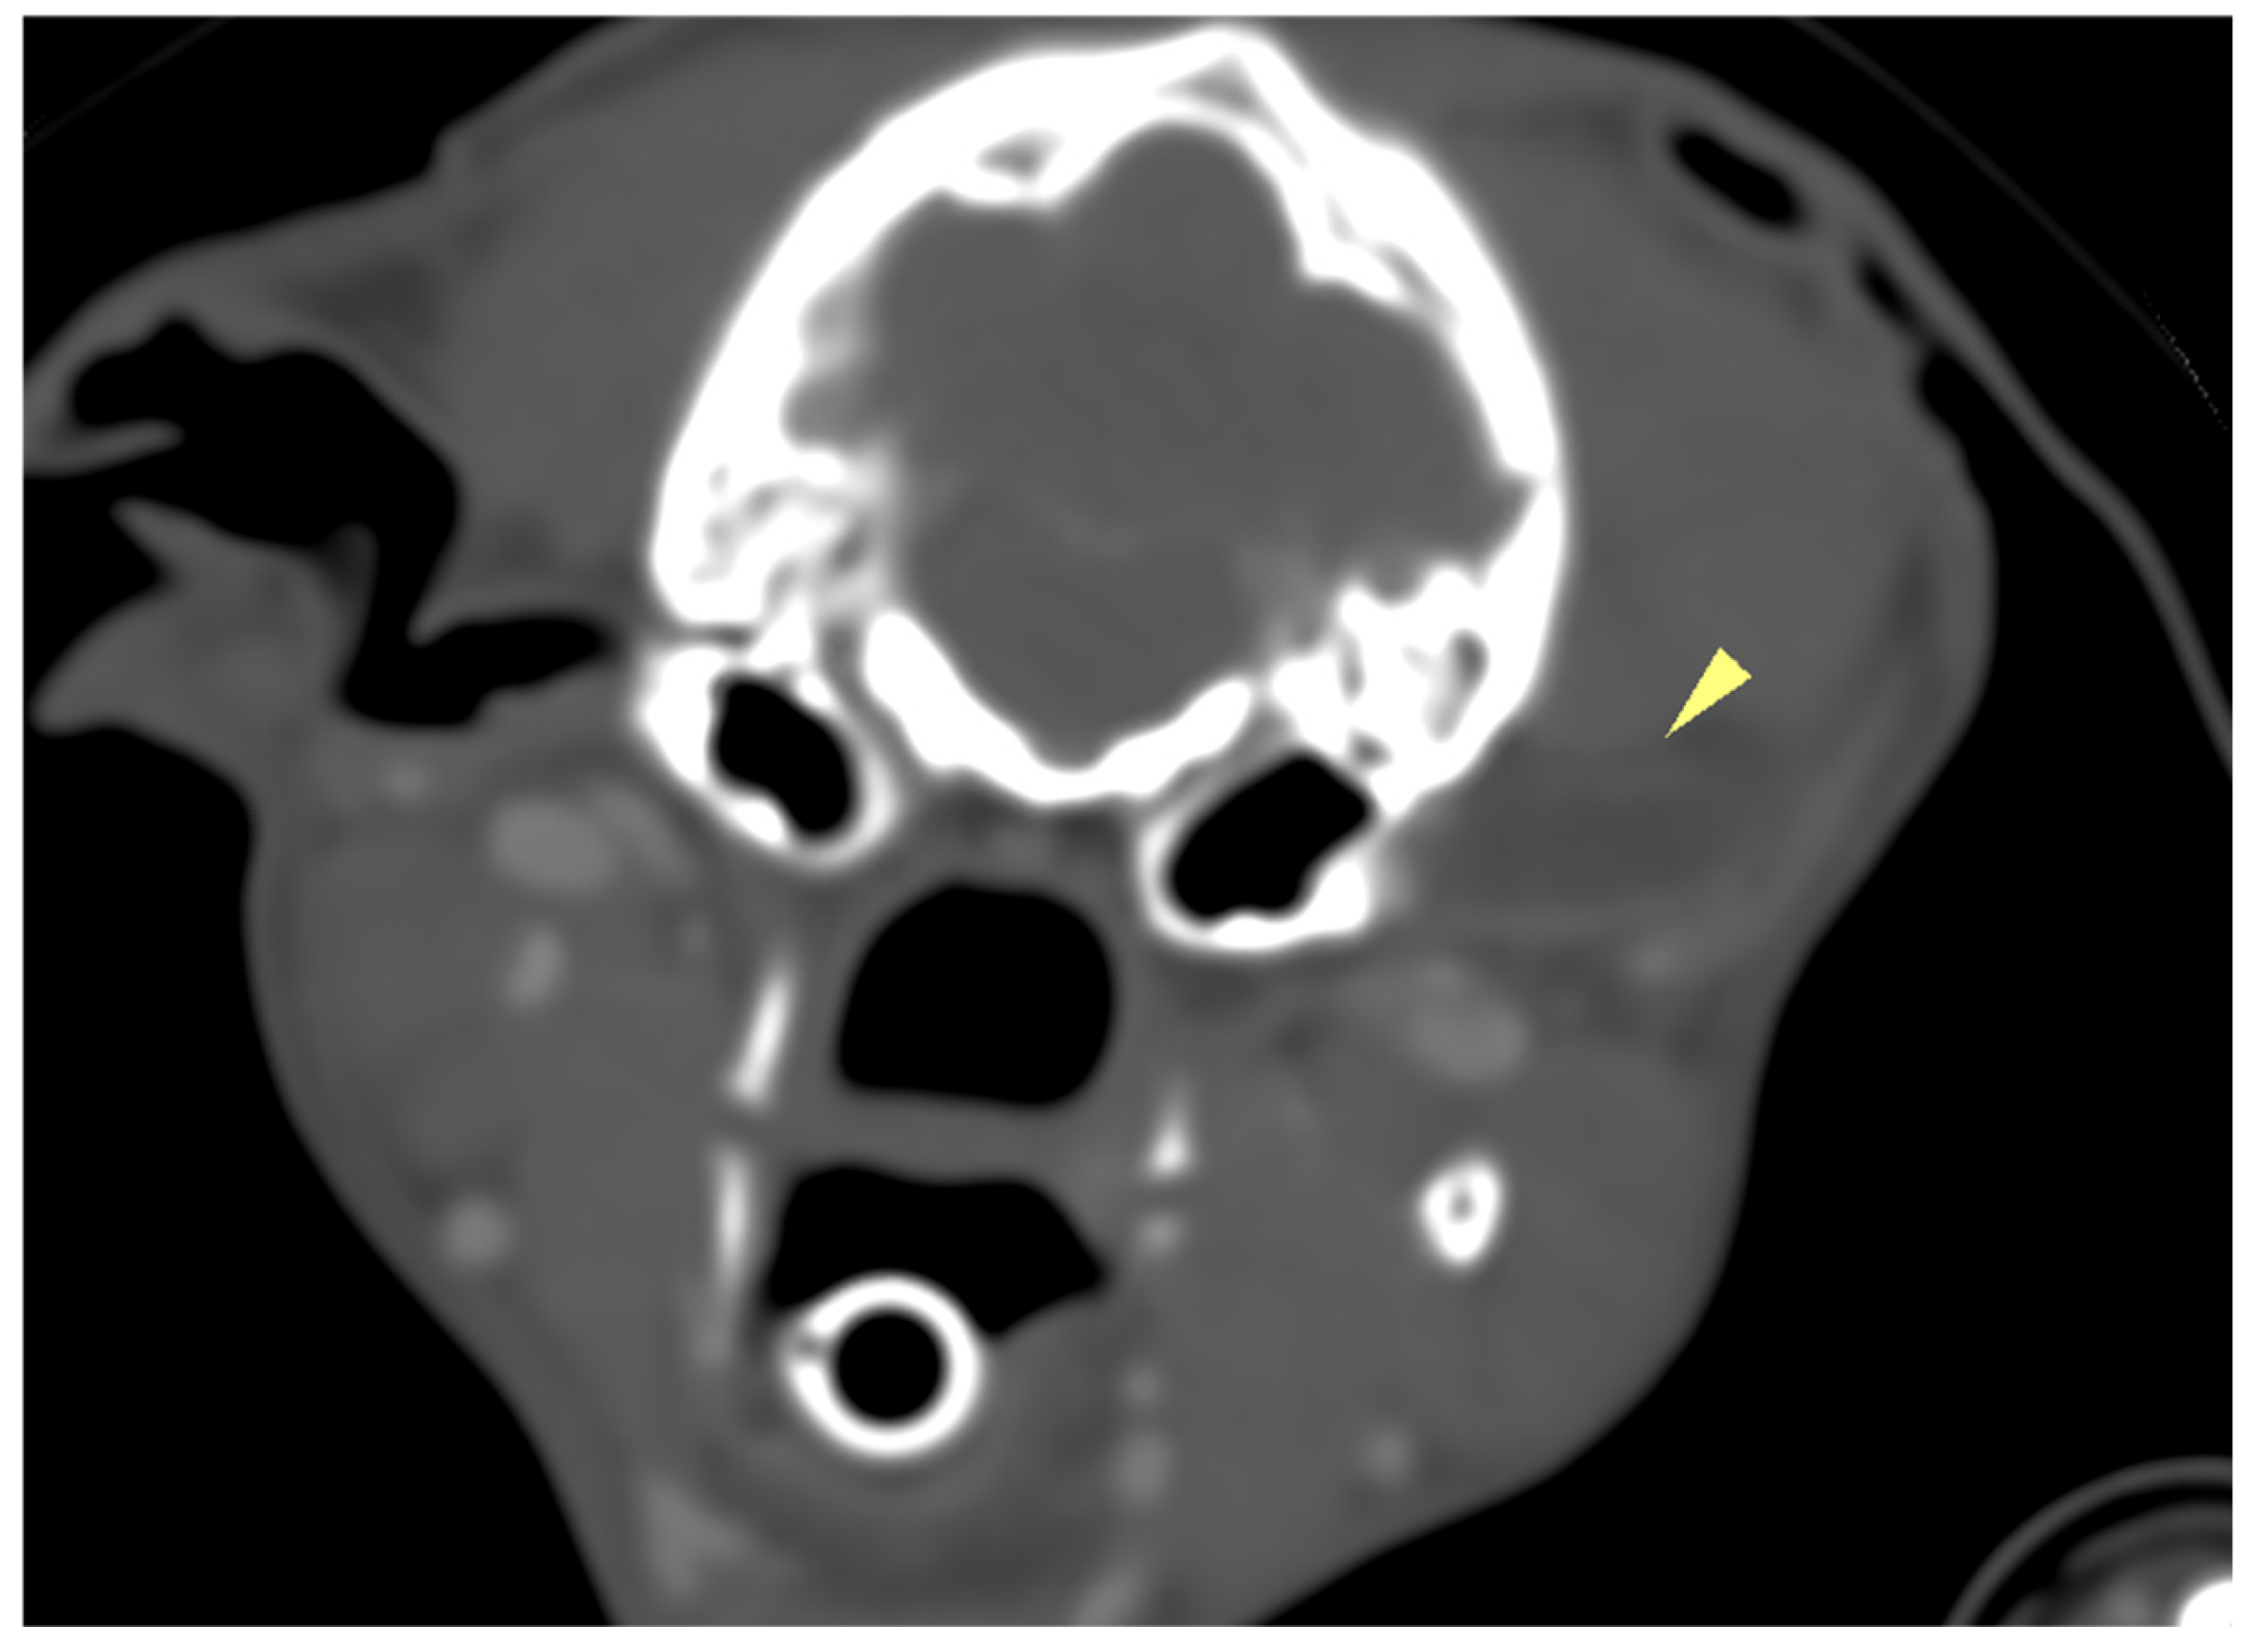

In case 2, CT findings revealed hypopneumatization of the left external ear canal, associated with the presence of intraluminal material exhibiting soft tissue attenuation, without any associated change in attenuation following intravenous contrast medium administration. The continuity between the horizontal portion of the left external ear canal and the auricular pinna could not be visualized (Figure 3). The contralateral ear canal and associated cavities appeared within normal limits. Pneumatization of the nasal cavities and the nasopharynx was preserved. The changes affecting the left external ear canal were compatible with atresia and secondary left external otitis.

Figure 3. Transverse plane computed tomography, in case 2, image showing hypopneumatization of the left external ear canal (yellow arrowhead), intraluminal material within the canal, and loss of continuity between the horizontal canal and auricular pinna.